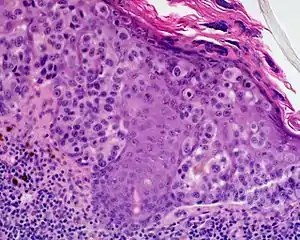

Lentigo maligna melanoma

Lentigo maligna melanoma is a melanoma that has evolved from a lentigo maligna,[1]:695 as seen as a lentigo maligna with melanoma cells invading below the boundaries of the epidermis.[2] They are usually found on chronically sun damaged skin such as the face and the forearms of the elderly.

Lentigo maligna is the non-invasive skin growth that some pathologists consider to be a melanoma-in-situ.[3] A few pathologists do not consider lentigo maligna to be a melanoma at all, but a precursor to melanomas. Once a lentigo maligna becomes a lentigo maligna melanoma, it is treated as if it were an invasive melanoma.

An invasive tumor arising from a classical lentigo maligna. Usually a darkly pigmented raised papule or nodule, arising from a patch of irregularly pigmented flat brown to dark brown lesion of sun exposed skin of the face or arms in an elderly patient.